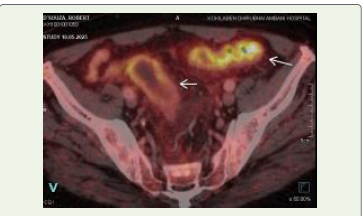

Case Presentation:A 75-year-old man presented with two months of progressive dysphagia, muscular twitching of the tongue, and weakness. Neurophysiology confirmed motor neuronopathy. PET CT revealed a carotid bifurcation mass and hypermetabolic rectosigmoid thickening. Biopsy of a cervical lymph node demonstrated moderately differentiated adenocarcinoma. Intravenous corticosteroids resulted in only partial improvement, but subsequent targeted radiotherapy to the primary malignancy led to marked and sustained recovery of bulbar and motor function.

Investigation findings are outlined in [Table 1].Clinical course:

Given high aspiration risk, an NG tube was inserted. He was

deficits persisted.Following confirmation of adenocarcinoma, the patient underwent targeted radiotherapy to the suspected rectosigmoid primary and regional nodes. In the weeks after radiotherapy, his bulbar function, swallowing, and gait improved significantly, and he was able to resume partial oral feeding. This dual pattern suggested an immune-mediated, paraneoplastic motor neuronopathy, partially steroid-responsive but substantially improved only after oncologic treatment.

Several features in this case strongly favored a paraneoplastic motor neuronopathy over classical ALS. The temporal profile was subacute, progressing over weeks rather than months to years. Neurological findings were predominantly lower motor neuron in distribution, without upper motor neuron signs, and remained nonprogressive over 12 months of follow-up. Anti-Hu antibody positivity provided serological evidence of a high-risk paraneoplastic antibody associated with malignancy-related neurological syndromes. There was a clear temporal association between neurological onset and the diagnosis of metastatic adenocarcinoma. Most importantly, the patient demonstrated partial responsiveness to corticosteroids and marked, sustained improvement following definitive tumor directed radiotherapy, an outcome incompatible with the natural history of classical ALS.